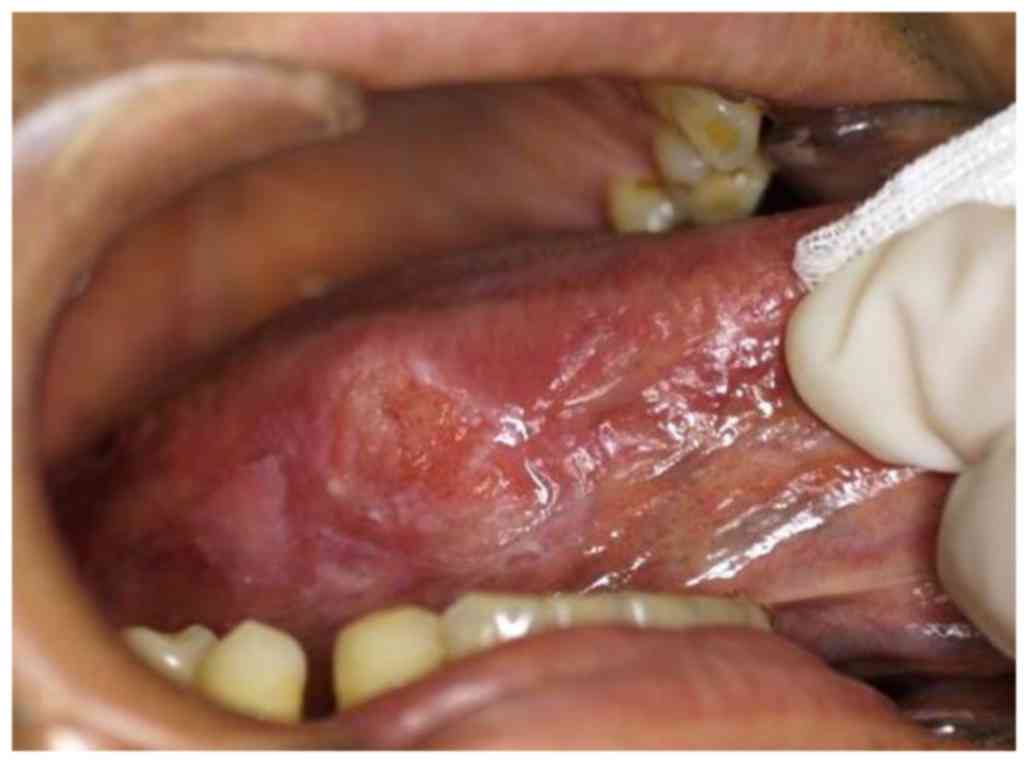

Kikuchi-Fujimoto disease in the regional lymph nodes with node metastasis in a patient with tongue cancer: A case report and literature review

Kikuchi-Fujimoto disease (KFD), also known as histiocytic necrotizing lymphadenitis, is a rare self‑limiting disorder typically affecting the cervical lymph nodes (LNs), which is often misdiagnosed as other LN‑associated diseases. KFD frequently presents with necrotic lesions and recurrences, which are also features of metastatic LNs. Clinicians may thus suspect LN metastasis when they encounter ipsilateral cervical lymphadenopathy in a patient with head and neck cancer. The present study reports the case of a 48‑year‑old man with tongue cancer and KFD affecting the right edge of his tongue and ipsilateral cervical LNs. LN metastasis was initially suspected, but pathological examination of the dissected LNs revealed one necrotic metastatic lesion and two necrotic KFD lesions. Ipsilateral cervical lymphadenopathy recurred 6 years after the initial surgery, and it was not possible to differentiate clinically between a second primary tumor and recurrent KFD prior to treatment. To the best of our knowledge, this is the first reported case of simultaneous tongue cancer, regional LN metastasis and KFD. This highlights the requirement to consider KFD in the event of LNs with necrotic lesions but no cancerous cells. A combination of clinical and pathological approaches may aid in the diagnosis of KFD, in addition to ruling out LN metastasis in initial and recurrent lymphadenopathies. The present study indicate that a diagnosis of KFD should be considered in patients with head and neck cancer that exhibit necrotic LNs lacking cancerous cells. This is important, as misdiagnosis of KFD as LN metastasis may lead to unnecessary adjuvant therapy.